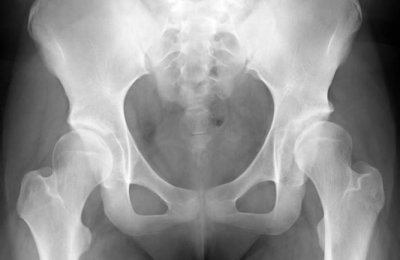

On your first visit we make a thorough clinical assessment of your situation and X-rays may be taken at that visit.